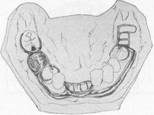

Fig. 5-35 Anatomic replica palatal major connector for a Class II, modification 1, partial denture. Anterior border avoids coverage of anterior rugae; posterior border lies well back on immovable hard palate, crossing midline at a right angle. Total contact provides excellent auxiliary retention without objec­tionable bulk.